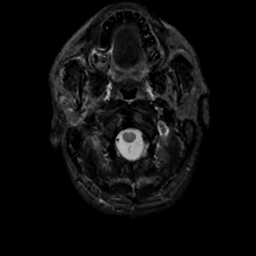

MR Study #12, May 12, 1991 -- Slice #1